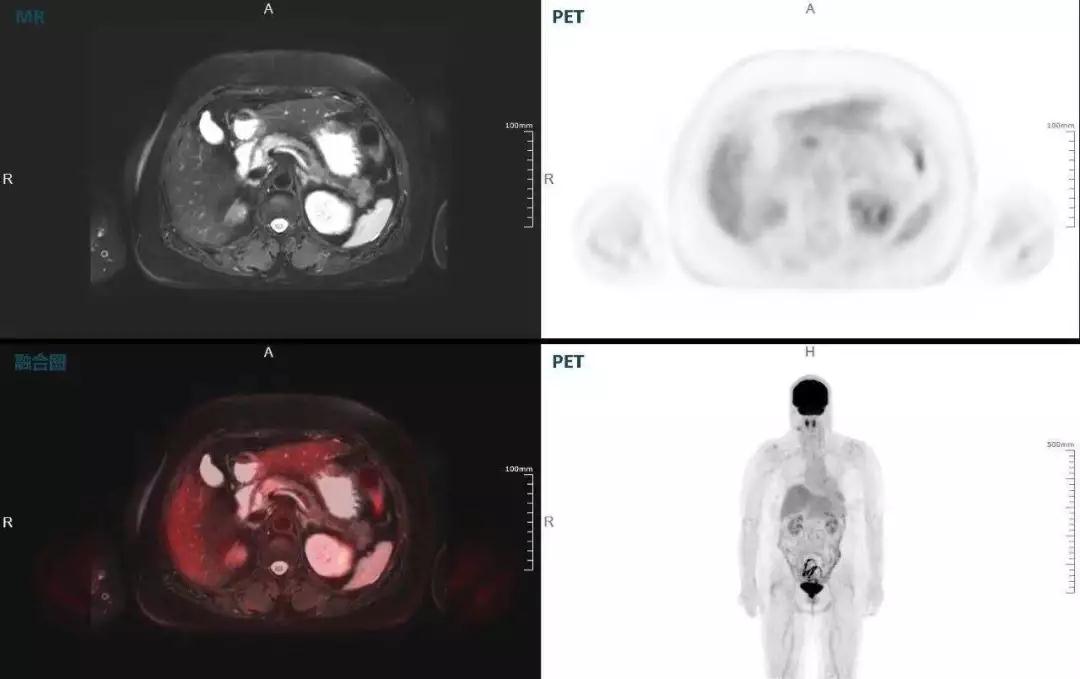

中山醫(yī)院核醫(yī)學(xué)科在臨床實(shí)踐中發(fā)現(xiàn),基于聯(lián)影“時(shí)空一體”超清TOF PET/MR,不僅解剖信息和代謝信息能夠完美融合呈現(xiàn),同時(shí)精細(xì)展示局部病灶與周圍組織的復(fù)雜關(guān)系,并能全盤檢測病灶的全身轉(zhuǎn)移,為醫(yī)生臨床診斷提供更豐富信息。

(胰腺腫瘤,MR顯示胰腺體部信號(hào)異常,PET顯示稍高攝取,結(jié)構(gòu)改變和功能異常提示胰腺M(fèi)T可能大。)